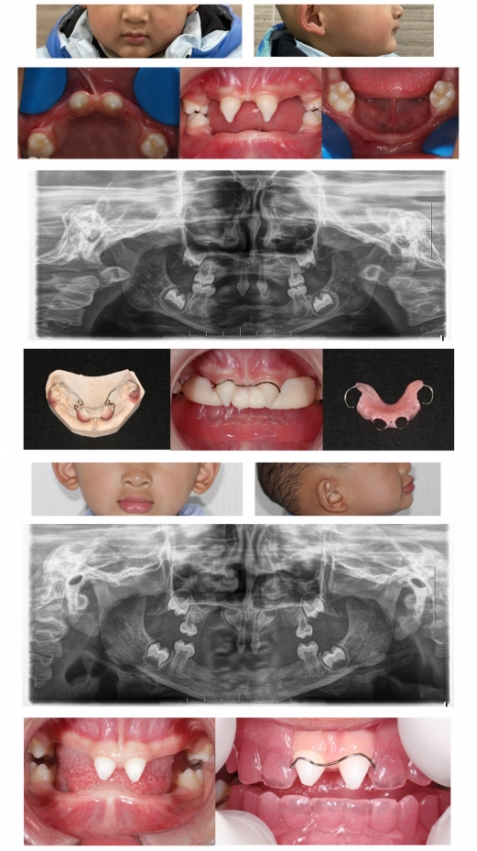

ED儿童通常在婴幼儿时期因汗腺发育不全而导致反复发烧,在牙发育期间,因牙胚部分甚至全部缺失而导致乳、恒牙无法萌出,使得面下部咀嚼功能受阻而导致发育不足,呈“瘪嘴 ”苍老面容,如头发稀少、卷曲,眉毛、睫毛稀缺,皮肤干燥,口周皮肤色素较深,上下唇呈外翻状。在影像学上呈现双侧颞下颌关节腔增大,牙胚缺失及牙槽骨、颌骨高度不足。

ED儿童早期修复治疗可以尽早改善发音、提高咀嚼效能,从而促进其颌骨及颜面部发育,利于美观和心理健康。修复最佳时机为四岁以上,患儿可自主配合口腔修复治疗,并且有自主佩戴义齿的能力,修复后能配合发音及咀嚼练习,家长能督促与指导。

由于低龄患儿牙弓较小,牙槽嵴条件较差,因此区别于常规义齿修复,需针对不同患儿,选用减数减径排牙、个性化自凝雕刻排牙、个性化热凝雕刻排牙等方式改良修复。